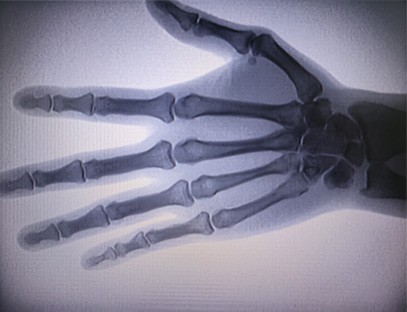

מכשיר רנטגן ניידהוא מינון קרינה נמוך, מכשיר נייד בטוח מאוד שיכול להשיג תמונות באיכות גבוהה תוך הפחתת החשיפה לקרינה. הוא מפצה על החסרונות של ציוד גדול בבית החולים וניתן להזיז אותו ולסחוב אותו בכל עת. מתאים במיוחד ליחידות וליחידים עם תקציב לא מספיק ודרישות נמוכות לתמונות. מכונת הרנטגן מהדור החדש שלנו מצוידת במסך גדול בחדות גבוהה בגודל 10 אינץ', בעל טווח זווית צפייה גדול יותר ויכול לראות באופן מלא דרך כל כף היד, כולל שברים, נקעים, דלקות פרקים וגידולי עצמות. ניתן לחבר אותו למדפסת סרטים להדפסת סרטים אורטופדיים, ויכול לשמש גם לייצור ובדיקות תעשייתיות. אין צורך בחדר חושך, פרספקטיבה ישירה, תצפית בזמן אמת. למכונה זו מערכת הדמיה ברזולוציה גבוהה שיכולה ללכוד תמונות של כל מבנה עצם בצורה ברורה מאוד. לספק את מיטב הציוד והפתרונות לבדיקת קרני רנטגן עבור יצרני מוצרים רפואיים, חיות מחמד, תעשייתיים, אלקטרוניים, מחלקות בדיקה ותחזוקה ומעבדות מחקר.

הִתמַחוּת:מיועד לצרכי מרפאות אורטופדיות, מתאים במיוחד להדמיית רנטגןשל גפיים כגון ידיים, פרקי כף היד, מרפקים, כתפיים, ברכיים, קרסוליים וכו'.

הדמיה ברורה:טכנולוגיית הדמיה דיגיטלית מתקדמת משמשת לספק תמונות רנטגן באיכות גבוהה, המסייעת לרופאים לאבחן במדויק את המצב.